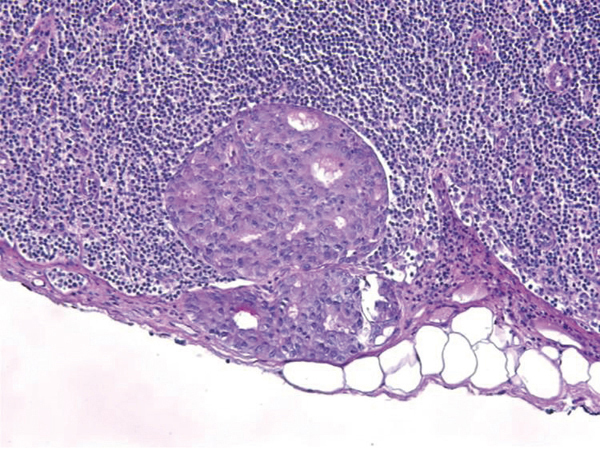

Tumeurs du sein - Coupe histologique d'un ganglion sentinelle montrant une micrométastase (< 2mm)

2. Tumeurs du sein - Coupe histologique d'un ganglion sentinelle montrant une micrométastase (< 2mm)